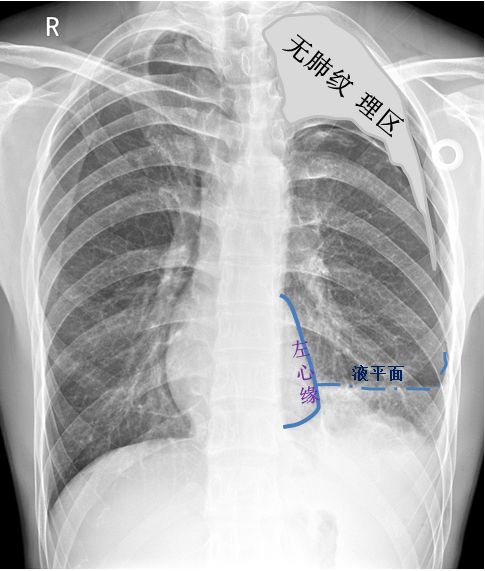

病例1患者的X线胸片

左上肺肺野可见肺叶压缩带边缘,肺叶压缩约30%(灰色区域)。左下肺野可见液-气平面,约与第5前肋相平(蓝色虚线),肺门影不浓。心影及纵隔向对侧轻度移位。

侧位片可见左侧肋膈角变钝,少量胸腔积液